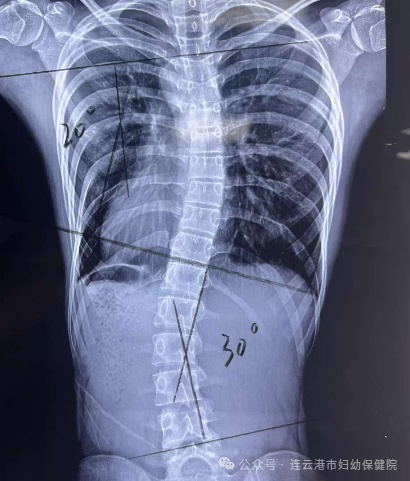

全脊柱X线影像学检查常用于AIS的筛查、手术及非手术治疗疗效的评估。通过确定侧弯段上下端,分别于上锥体上缘、下锥体下缘做平行线,并垂直于平行线做垂线形成夹角(Cobb角,如图3)。全脊柱X线下冠状面横向侧凸超过10°(Cobb>10°)是诊断侧弯的“金标准”。同时可评价髂骨骨骺发育情况,进行Risser评级,评估脊柱侧弯恶化风险。

对于Cobb角<20°的轻度侧弯,建议定期随访观察即可,一般建议3-6个月评估一次。观察过程中配合一系列物理治疗,主要包括跑、跳及游泳等体育锻炼、中医推拿,以达到增强脊柱周围肌肉的力量、改善脊柱的稳定性和平衡的目的。

适用于20°<Cobb角<44°的生长发育期、青春期患者,通过佩戴矫形器对脊柱施加持续、稳定的矫形,帮助患儿慢慢挺直腰杆。

对于脊柱侧弯Cobb角≥45°或保守治疗后进行性加重的患者,可通过手术治疗,改善患者外观、稳定躯干平衡、延缓脊柱弯曲进展,降低AIS短期或长期并发症发生率。